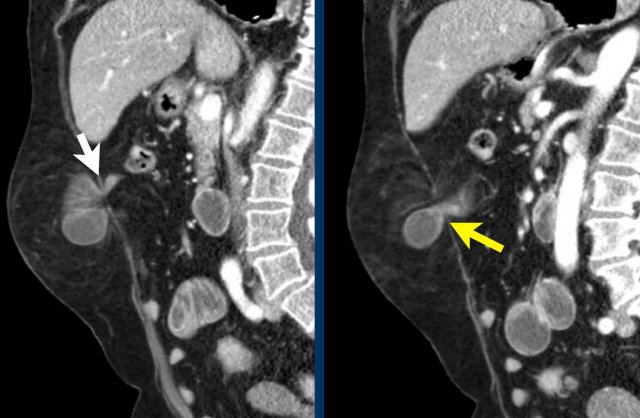

This patient has a hernia that contains small bowel.

The defect is rather small and there is a stenosis at the point where the bowel enters the hernia sac (yellow arrow) and where it exits the hernia (white arrow).

These two stenosis are proof of a closed loop obstruction.

There is dilatation of the bowel and fat infiltration as a result of ischemia resulting from venous obstruction.

Continue with the video...

The video better demonstrates the two stenoses.